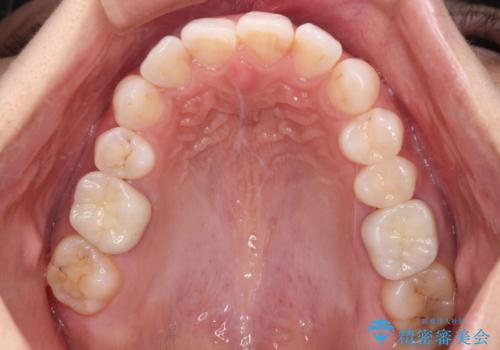

- 奥歯の銀歯が外れたことをきっかけに、全ての銀歯をセラミックに替えたいとのことで来院された患者様です。

第一大臼歯4本と、メタルインレーが装着されている2歯をセラミッククラウンならびにセラミックインレーにて補綴治療・修復治療を行うこととしました。

口腔内から、土台も含め銀歯がなくなったことでメタルフリーとなりました。